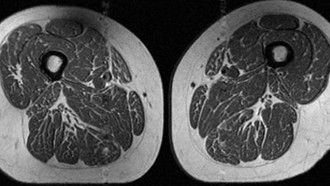

Ảnh minh hoạ.